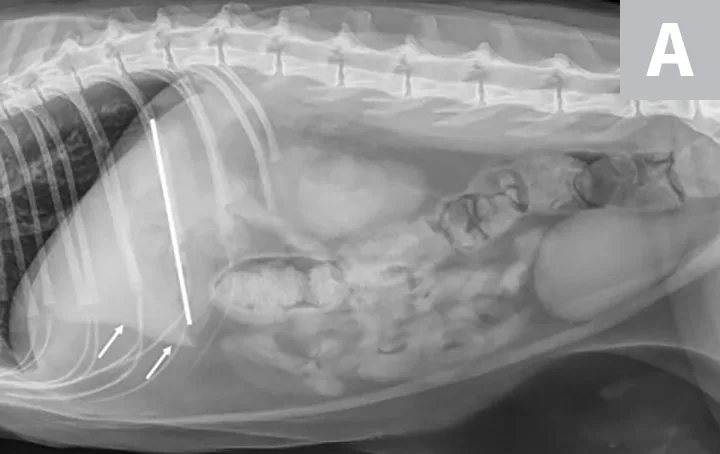

Lateral radiographs of a clinically normal cat (A) and a 14-year-old neutered male domestic shorthair cat (B) presented with icterus and elevated liver enzymes. A normal feline liver should have a sharp, pointed margin (A; arrows) and should not extend past the costal arch; the gastric axis should be parallel to the ribs (A; line). The liver in the icteric cat extends past the costal arch, and has rounded borders (B; arrows). The stomach is displaced caudally (B; line; gastric axis from the fundus to the antrum). An ovoid mineralization (B; arrowheads) is also superimposed with the cranioventral liver in the location of the gallbladder. This cat was diagnosed with cholangitis, lipidosis, and a cholelith.